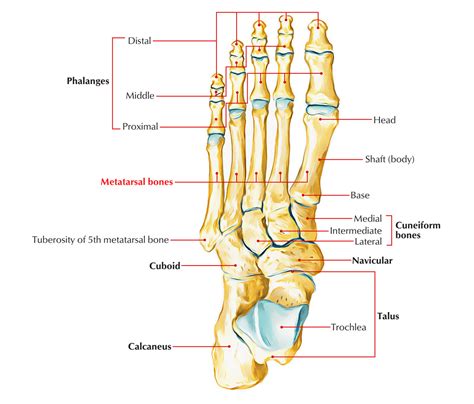

The metatarsophalangeal (Mtp) joint is the joint where the metatarsal bones of the foot meet the phalanges of the toes. This joint is essential for the foot’s range of motion and stability. The Mtp joint allows the toes to bend and straighten, which is vital for activities like walking, running, and jumping. Any disruption or injury to this joint can lead to significant discomfort and mobility issues.